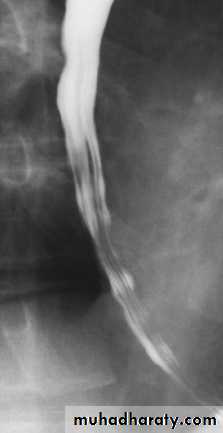

Barium swallow

• Its contrast examination of the esophagus.

• Barium swallow is a relatively simple and noninvasive investigation in which the patient is asked to swallow liquid barium and images are obtained as it passes through the esophagus.

Barium examination

Technique of examination.Normal anatomy:

straight parallel lines.

External impression.